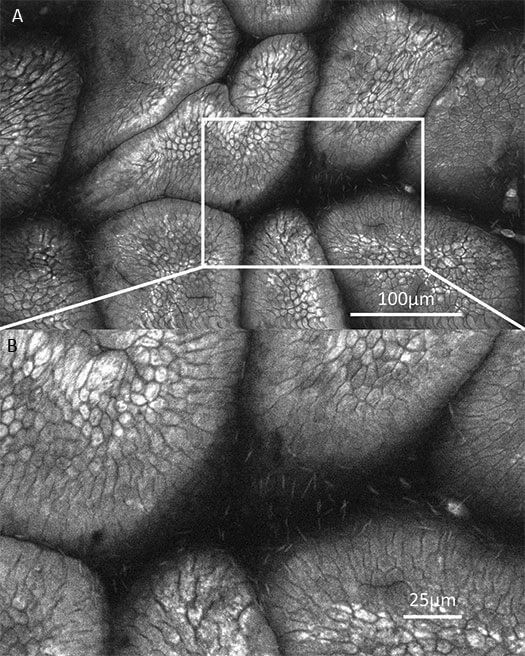

1、口腔癌OptiScan成像

左:正常组;中:癌前期组;右:癌变组。

注:Optiscan技术可以实时捕捉口腔黏膜的亚细胞细节,而无需进行活组织检查。Scale bar=100μm。